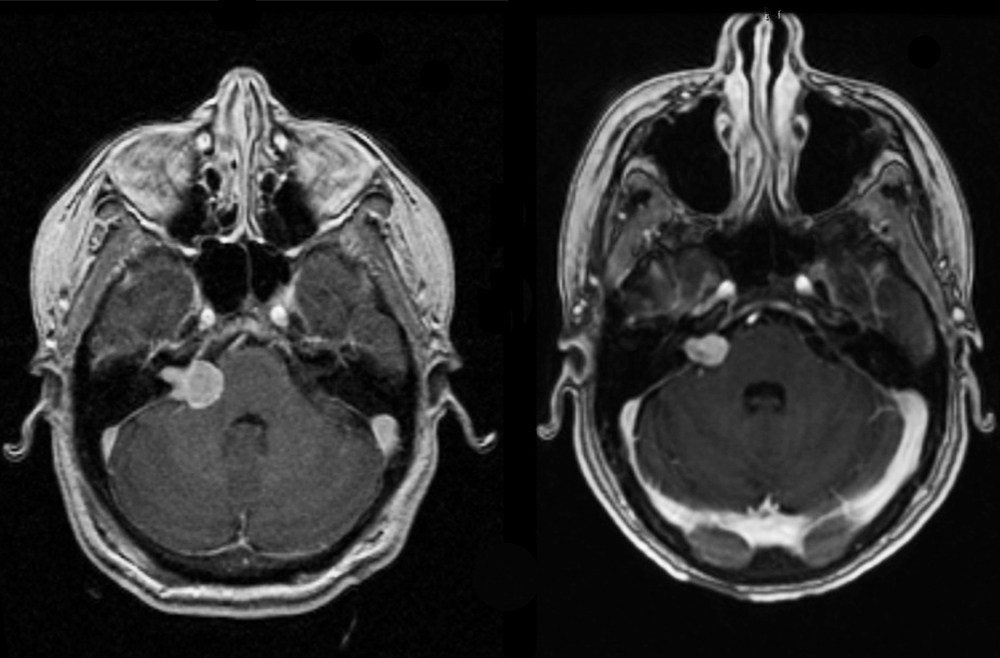

Acoustic neuroma / Vestibulocochlear schwannoma

Cerebellopontine angle

The angle between the cerebellum pons, and temporal lobe

This space contains cranial nerves V through XI